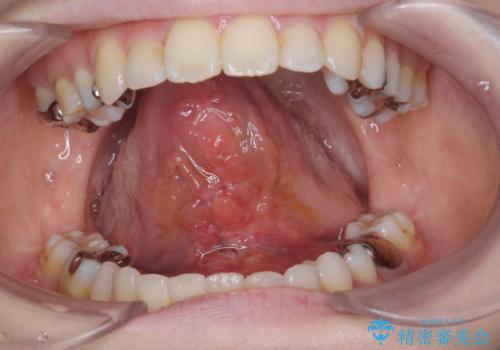

[滑舌を治したい] 舌の小帯の形成術

担当医 大元洋佑

![[滑舌を治したい] 舌の小帯の形成術の症例 治療前](https://seimitsushinbi.jp/wp/wp-content/uploads/2023/11/IMG_8451-500x350.jpg?v=1699614841)

![[滑舌を治したい] 舌の小帯の形成術の症例 治療後](https://seimitsushinbi.jp/wp/wp-content/uploads/2023/11/IMG_8901-500x350.jpg?v=1699614854)